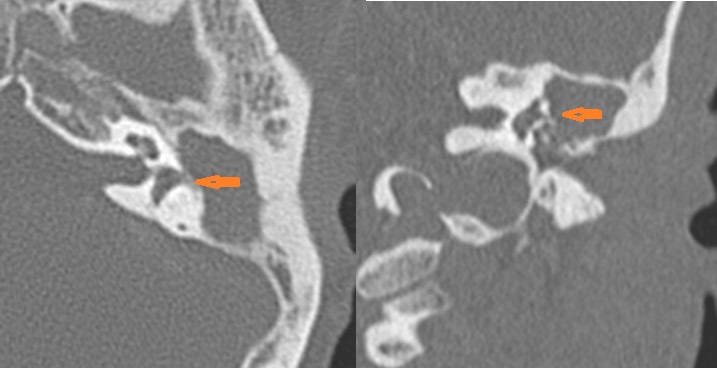

18-year-old female presenting to the emergency room with severe right-sided headache, mastoid region tenderness and swelling and fever, dizziness with possible meningitis. Study is done to look for evidence of coalescent or otherwise complicated mastoiditis as a cause for these symptoms.Exam

Contrast-enhanced CT of the temporal bone and related anatomy with images obtained in the balanced or venous vascular phase to ensure optimal visualization of the dural venous sinuses. 0.5-1.0 mm thick sections were obtained in the axial plane and reformatted 3D and/or in the coronal and sagittal planes and viewed inter actively in 3 dimensions at the computer work station.